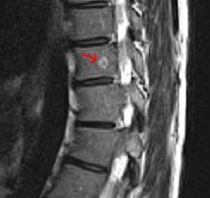

Bei Zysten oder Vernarbungen im Bereich des Gehirns hindeuten. Zur weiteren Differenzierung zwischen den Ursachen der Flecken sind Tests erforderlich die in der Regel durch einen Neurologen durchgeführt werden. Das Rückenmark als Schlüssel zur MS-Diagnostik. MRT der LWS T2 linkes Bild Weiß kann man die Entzündung der Lendenwirbelsäule erkennen da die Bandscheibe durch die Fehlstellung aufgebraucht wurde und nun Knochen auf Knochen reibt und eine Entzündung des Knochens entsteht. Ich habe viele mrt bilder von mir daheim. 7 Wochen ein MRT der HWS mit der Diagnose Foraminastenose bds cervicaler Bandscheibenschaden Z. Ein Computer wandelt diese Signalen in sichtbare Bilder um.